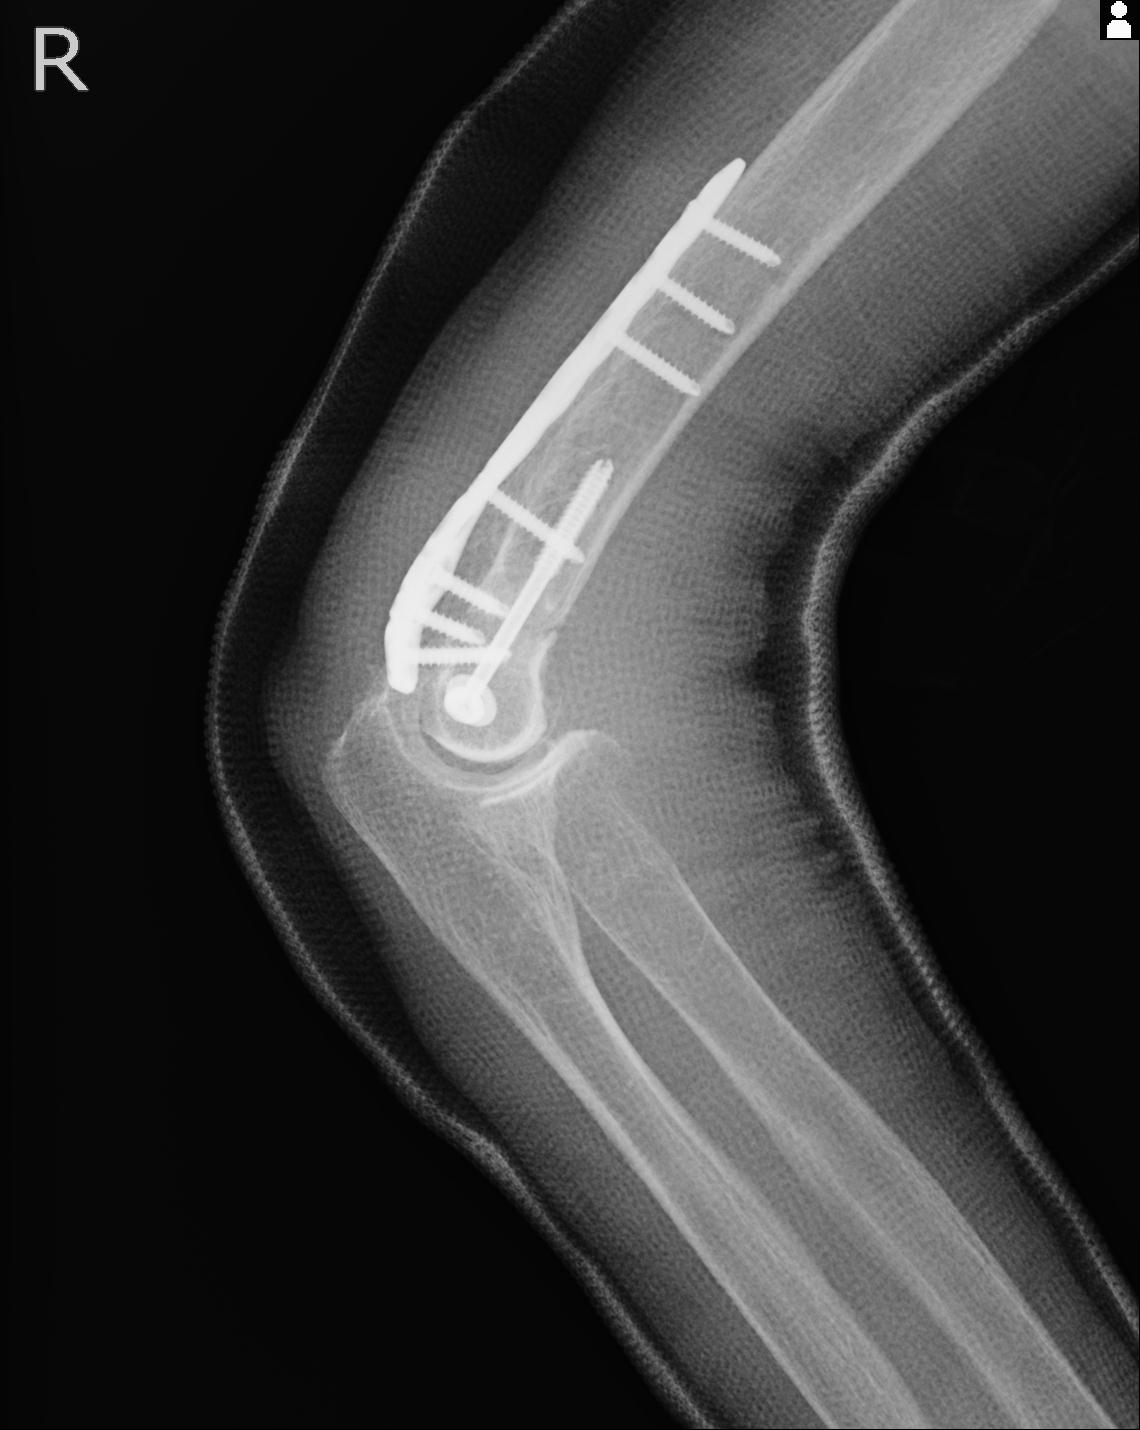

2271 1/25 右肘 4R 1/27 4R 3/24 4R 94歳女性 右通顆骨折